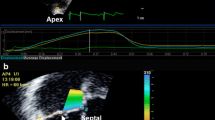

SASHA T 1 mapping method in a subject 15 minutes post-contrast. On each of 10 saturation recovery images, the endocardium, epicardium and a region of interest in the blood are selected. The myocardium is automatically divided into 18 circumferential segments and T1 values are calculated in each segment by fitting a recovery curve as described in the methods. Average signal intensity in a septal segment (white box, far right image) are shown along with a best-fit saturation recovery curve. S is the measured signal intensity normalized to the non-saturated image intensity, η is the best-fit saturation efficiency, TS are saturation recovery times and T1 is the best fit T1 value.

A sample T1 saturation recovery curve from a single segment as indicated, is shown in Figure 1. Figure 2 shows a representative example of best-fit baseline and post-contrast myocardial and blood T1 values, with the 18 segment format shown in A) and C), and with corresponding T1 pixel maps in B) and D). Figures 2E) and 2F) show the calculated ECV for this representative example in the18 segment and pixel map formats. Pixel formats are shown here for illustrative purposes. Average baseline T1 values (1155.3 ± 56.5 ms) were similar to previous reports using the same method [12, 13]. The ECV (20.7 ± 3.6%) was comparable to previous studies in younger adults [14]. Females showed increased non-contrast T1 (1191.7 ± 50.0 ms vs 1122.8 ± 37.9 ms) and ECV (23.0 ± 3.7% vs 18.7 ± 3.1%) compared to males.